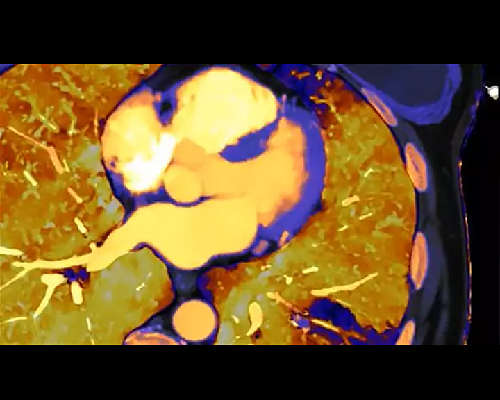

Deep clinical insights

Answer challenging diagnostic questions and significantly impact patient outcomes through the power of spectral-detector CT, which means that every scan for every patient gives you spectral results, allowing you to see more.